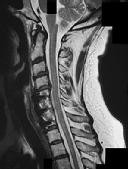

Figures 1 and 2 are CT scans obtained from a 68-year-old man who has had

progressive neck pain and stiffness, worsening gait imbalance, upper extremity weakness, early muscle fatigue, difficulty with fine motor control, and difficulty with activities of daily living over the past few years. On physical examination, he has a wide based stiff legged gait, generalized upper extremity weakness, dense sensory loss in the upper and lower extremities, and markedly brisk reflexes. What is the most appropriate treatment for this patient?

4. Posterior cervical laminoplasties from C3-6 Discussions: D

This patient has progressive myelopathy secondary to ossification of the posterior longitudinal ligament. Diagnostic imaging reveals multilevel cervical cord compression from C4-6. The patient has maintained reasonable cervical lordosis. A posterior procedure such as multilevel laminoplasty

decompresses the spine, is motion preserving, and has a low complication rate. Observation and cervical epidural injections are not viable options in patients with progressive myelopathy. Anterior cervical decompression, including corpectomy, is an option; however, anterior procedures have an increased risk of complications such as dural tear or cerebrospinal fluid leak. The axial CT image shows a "double layer" sign, which is consistent with dural ossification and increases the risk of dural injury with anterior decompression